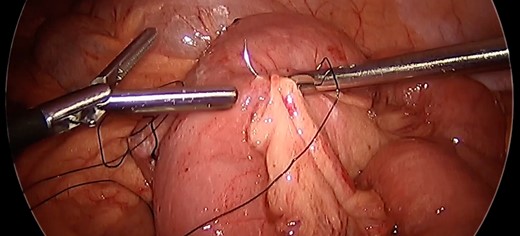

Given the propensity of the distal Roux limb to intussuscept into the enteroenterostomy, enteropexy was performed to eliminate its travel past the anastomosis. The distalmost aspect of the Roux limb was sutured with two pieces of running 3-0 silk to the end of the staple line on the biliopancreatic limb. Two additional sutures were placed slightly more upstream anchoring the roux limb to the mesentery of the transverse colon. An additional 3-0 silk suture was placed on the opposite side of the distal Roux limb anchoring it to the nearby mesenteric root. (Fig. 3) A 3–0 silk suture was placed to fix the common channel to the biliopancreatic limb to similarly limit the risk for intussusception of that limb. After this procedure, the small bowel was immobilized such that there was no longer predisposition for intussusception at the Roux-en-Y enteroenteric anastomosis (Fig. 4).

Anchoring bowel to mesenteric root. Nonabsorbable polyfilament suture placement between bowel and nearby mesenteric root limiting bowel mobility toward the anastomotic junction to prevent intussusception.

After enteropexy. Demonstration of nonabsorbable suture placement for enteropexy and subsequent inability to intussuscept the common limb into the enteroenteric anastomosis.